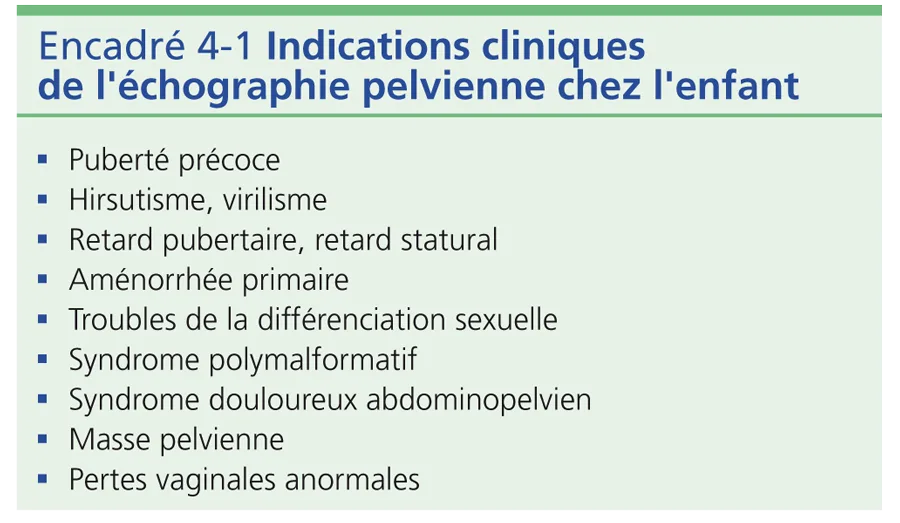

Enfin, l’existence d’un reflux d’urine dans le vagin est banale. Il peut simuler un hydrocolpos mais disparaît après miction ou en position debout (fig. 4-9). Les principales indications de l’échographie pelvienne chez l’enfant sont mentionnées dans l’encadré 4-1.

L’apparition des caractères sexuels secondaires survient entre 8,5 et 13 ans chez 95 % des filles et débute par une poussée mammaire. Pour mémoire, chez 95 % des garçons, le début de la puberté dont témoigne le développement testiculaire se situe entre 10 et 13,5 ans. L’accroissement progressif de la pilosité pubienne, le développement mammaire, testiculaire et pénien sont cotés selon les 5 stades de Tanner (fig. 4-10). La durée moyenne entre la poussée mammaire initiale et les menstruations est d’environ 2 ans. Chez le garçon, le développement pubertaire est en moyenne complet en 3 ans. Parallèlement, se produit une accélération de la vitesse de croissance staturale avec une maturation osseuse progressive cotée sur la radiographie de la main selon l’atlas de Greulich et Pyle.

Puberté précoce La précocité pubertaire se définit comme l’apparition des caractères sexuels secondaires avant 8 ans chez la fille et 10 ans chez le garçon. Elle est bien plus fréquente chez la fille que chez le garçon. Dans le bilan pratiqué, la place de l’échographie pelvienne est prépondérante car cet examen simple et reproductible permet de juger rapidement du degré du développement utéro-ovarien et de distinguer ainsi les vrais développements pubertaires des variantes cliniques du développement pubertaire, partielles et régressives, sans signification pathologique.